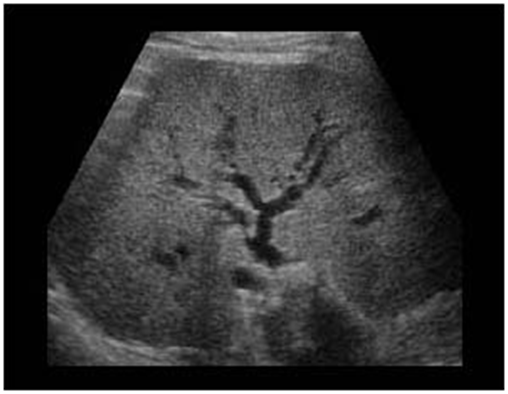

1. Pancreatic duct dilatation (Figure 3) (Figure 4)

Figure 3 Dilatation of the Wirsung duct, cancer in the head.

Figure 4 Dilatacion of the Wirsung duct, big cancer in the head